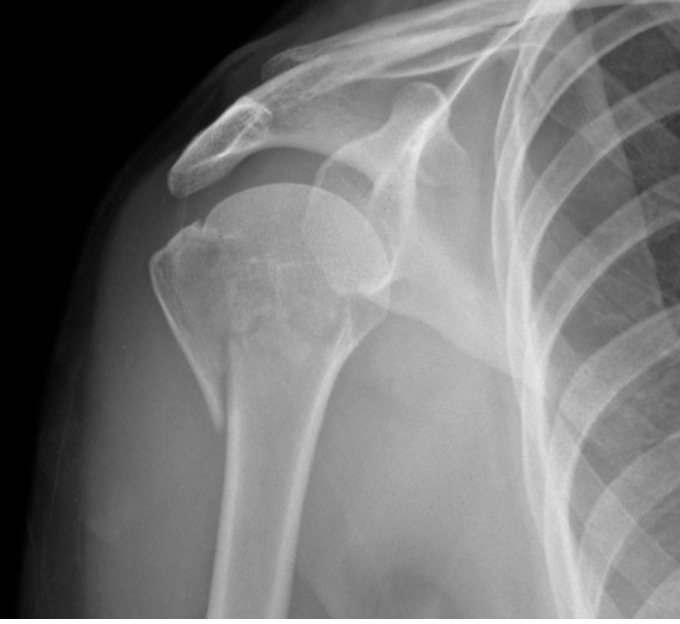

Transverse fractures of the surgical neck (red line)

Fracture line (yellow) causing separation of the greater tubercle

there is only minor displacement with moderate impaction and angulation (~30 degrees), with the glenohumeral joint remaining enlocated.

This would be considered a one-part fracture, as although both a greater tuberosity and surgical neck of humerus fracture are present neither are significantly displaced (<1cm) nor are they significantly angulated (<45 degrees).